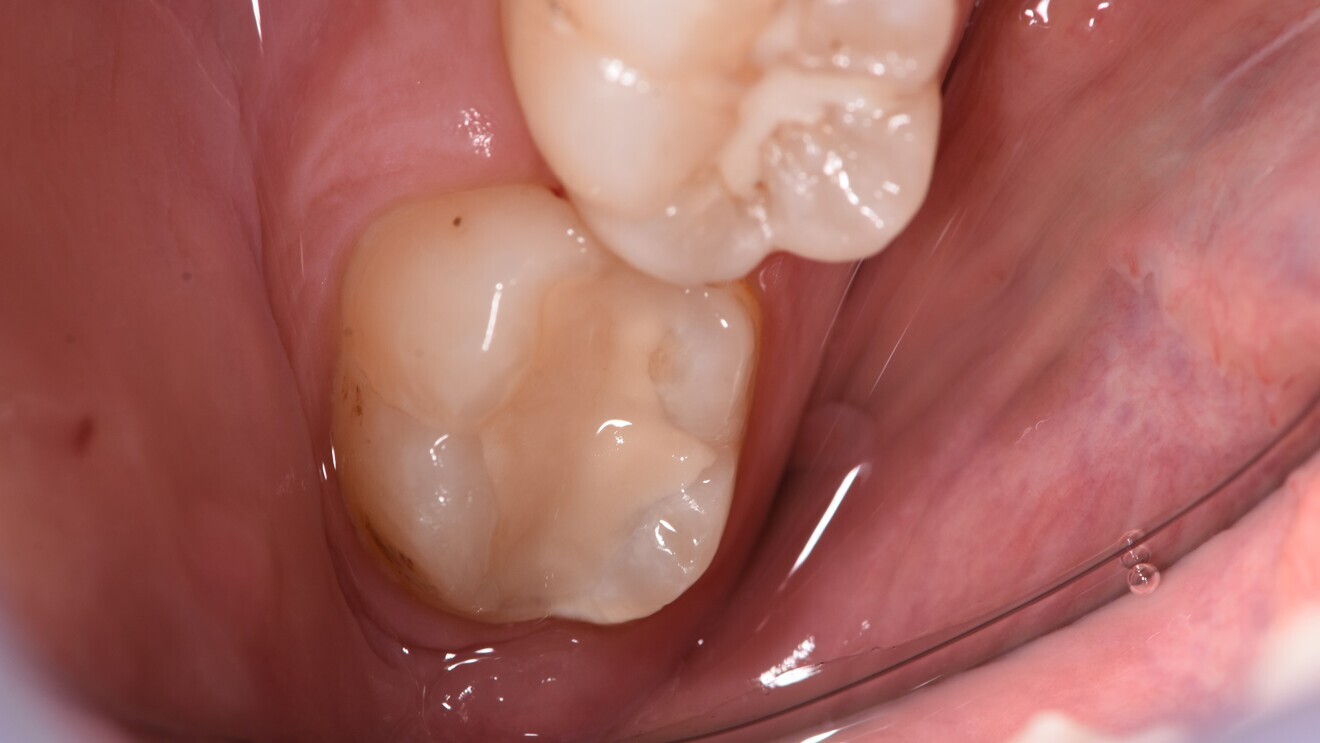

Fig. 9: Class II glass hybrid restoration five years after treatment.

A multinational randomised controlled split-mouth trial in four university hospital centres in ZagrebCroatia, Belgrade in Serbia, Milan in Italy and Izmir in Turkey compared a glass hybrid (EQUIA Forte) against a nano-hybrid composite (Tetric EvoCeram, Ivoclar) for a similar indication.9, 10 The study involved occlusal-proximal two-surfaced restorations in the molar region in adults with a permanent dentition; each individual needed to have two similar cavities in vital (positive response to ethyl chloride) molars of the same jaw to allow for the split-mouth design. A total of 360 restorations were placed in 180 patients. Per patient, one tooth was randomly selected to be restored with the glass hybrid and the other with the composite. Pre-contoured sectional matrices were employed and cavities conditioned according to the manufacturer’s instructions prior to placing the material. For the composite, a two-step self-etching adhesive (Adhese Universal, Ivoclar) was employed. Patients were followed up after one week, one year, two years and three years and the restorations assessed using the FDI criteria. Additionally, the costs of each restoration from the patient’s perspective were calculated, accounting for direct medical costs. To assess cost-effectiveness, incremental cost-effectiveness ratios were used, expressing the cost difference according to gained or lost effectiveness.

In that trial, patients in Italy were older than in the other centres, and overall, more patients were female than male. Thirty-two patients dropped out over the three-year period, and 21 received retreatments of 27 restorations. The mean survival time of the restorations was high across all centres and did not differ significantly between the two materials (Table 1). In three of the countries, the composite was more expensive both initially and over the long term (over the three-year follow-up and accounting for managing complications too). When assessing the cost-effectiveness (in US$ and survival in months), the composite was usually more costly than the glass hybrid in three of the countries. Overall, each additional month without complications for the composite compared with the glass hybrid group cost US$270.

The emerging body of evidence demonstrates that the glass hybrids are also promising for posterior, proximally extended cavities. While there are some inconsistencies regarding the comparative longevity of glass hybrids versus composites for this purpose between the two studies described, the results of the large multinational trial especially are assuring. In four independent centres, concordant results were generated, confirming that both the composite and glass hybrid were suitable materials for load-bearing cavities over the three-year observational period. Notably, the cost-effectiveness of glass hybrid was once more confirmed, deeming it a particularly good amalgam alternative when cost considerations are important, for example in low- and middle-income countries but also in most statutory or social insurance settings in high-income countries. Using an extrapolation model, it was further demonstrated that this cost-effectiveness was likely to be retained in the long term. A 2021 study found the added effectiveness of the composite to be minimal but also more costly than the glass hybrid.11 In sensitivity analyses, and under certain assumptions, the glass hybrid was even more effective and still less costly than the composite.